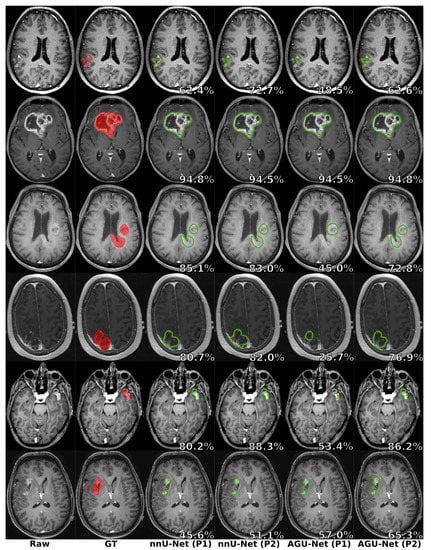

5.4. Preprocessing Impact

| Configuration | Pixelwise | Patientwise (PW) | |||||

|---|---|---|---|---|---|---|---|

| Dice | Dice-TP | HD95 | FPPP | F1 | Recall | Precision | |

| nnU-Net/GS1/P1 | |||||||

| nnU-Net/GS1/P2 | |||||||

| AGU-Net/GS1/P1 | |||||||

| AGU-Net/GS1/P2 | |||||||

| nnU-Net/GS2/P1 | |||||||

| nnU-Net/GS2/P2 | |||||||

| AGU-Net/GS2/P1 | |||||||

| AGU-Net/GS2/P2 | |||||||